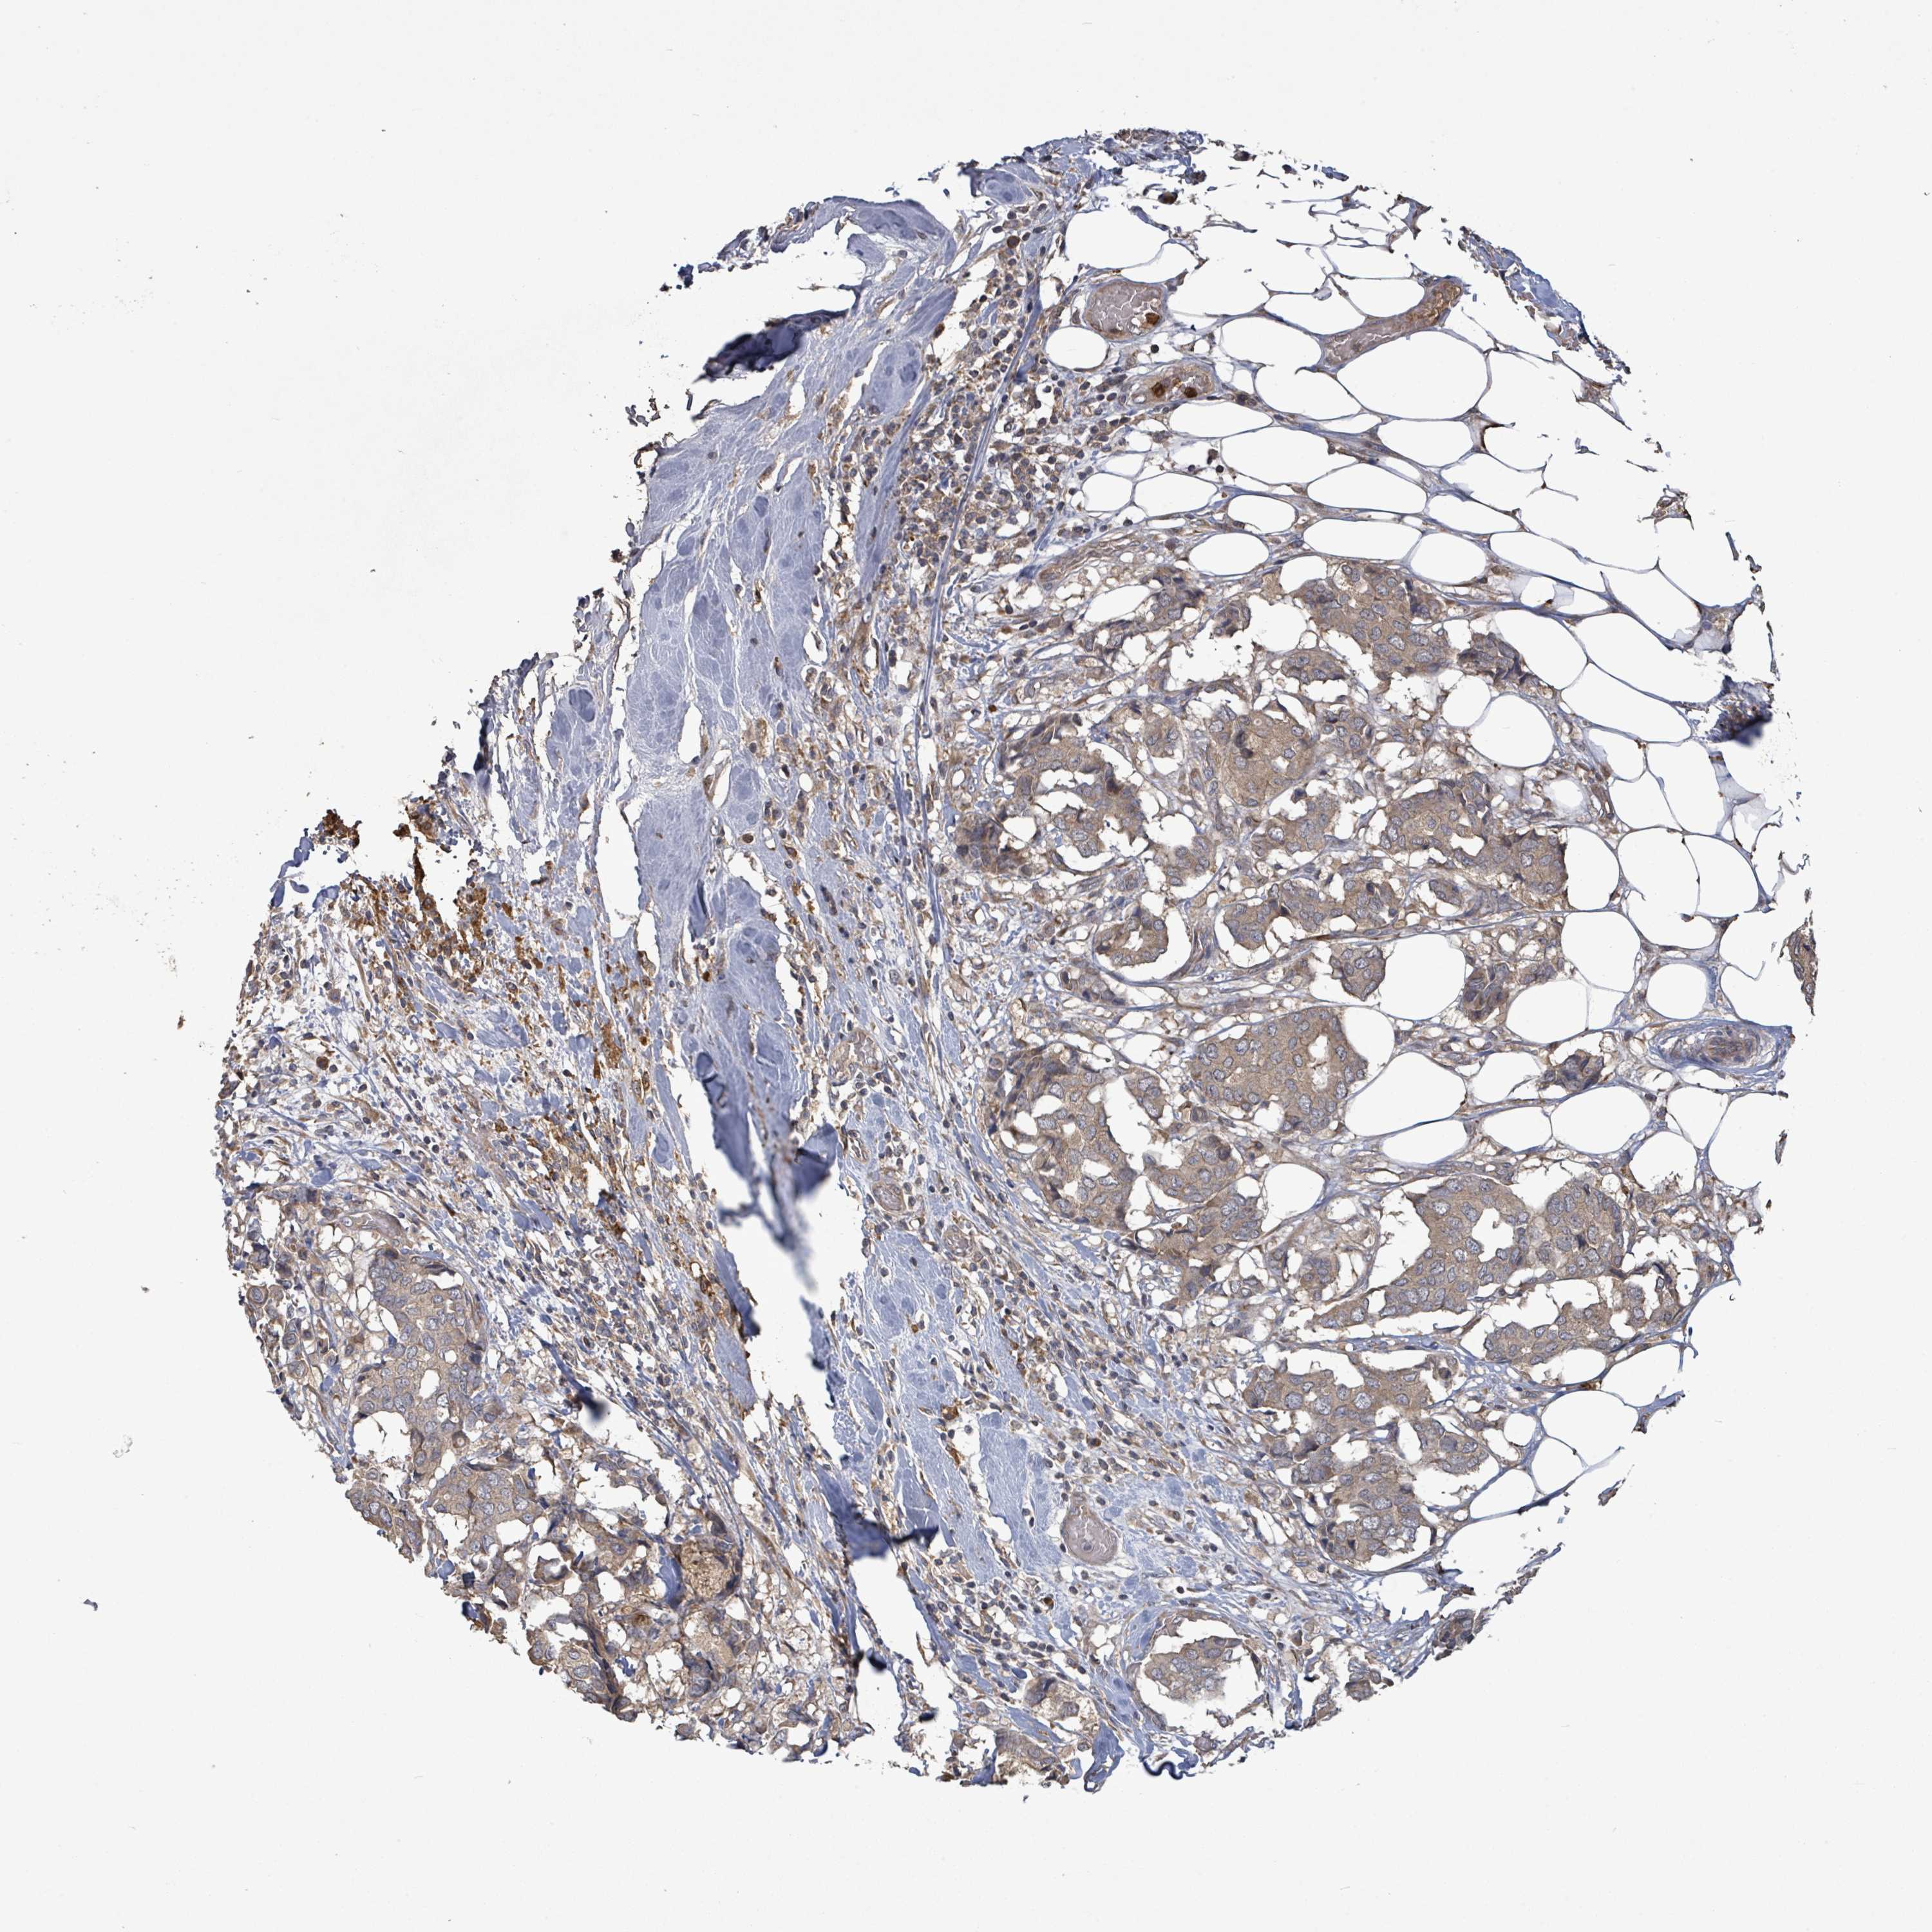

BRCA TCGA BRCA VALIDATION PROTEIN EXPRESSION

ANTIBODIES

AND

VALIDATION